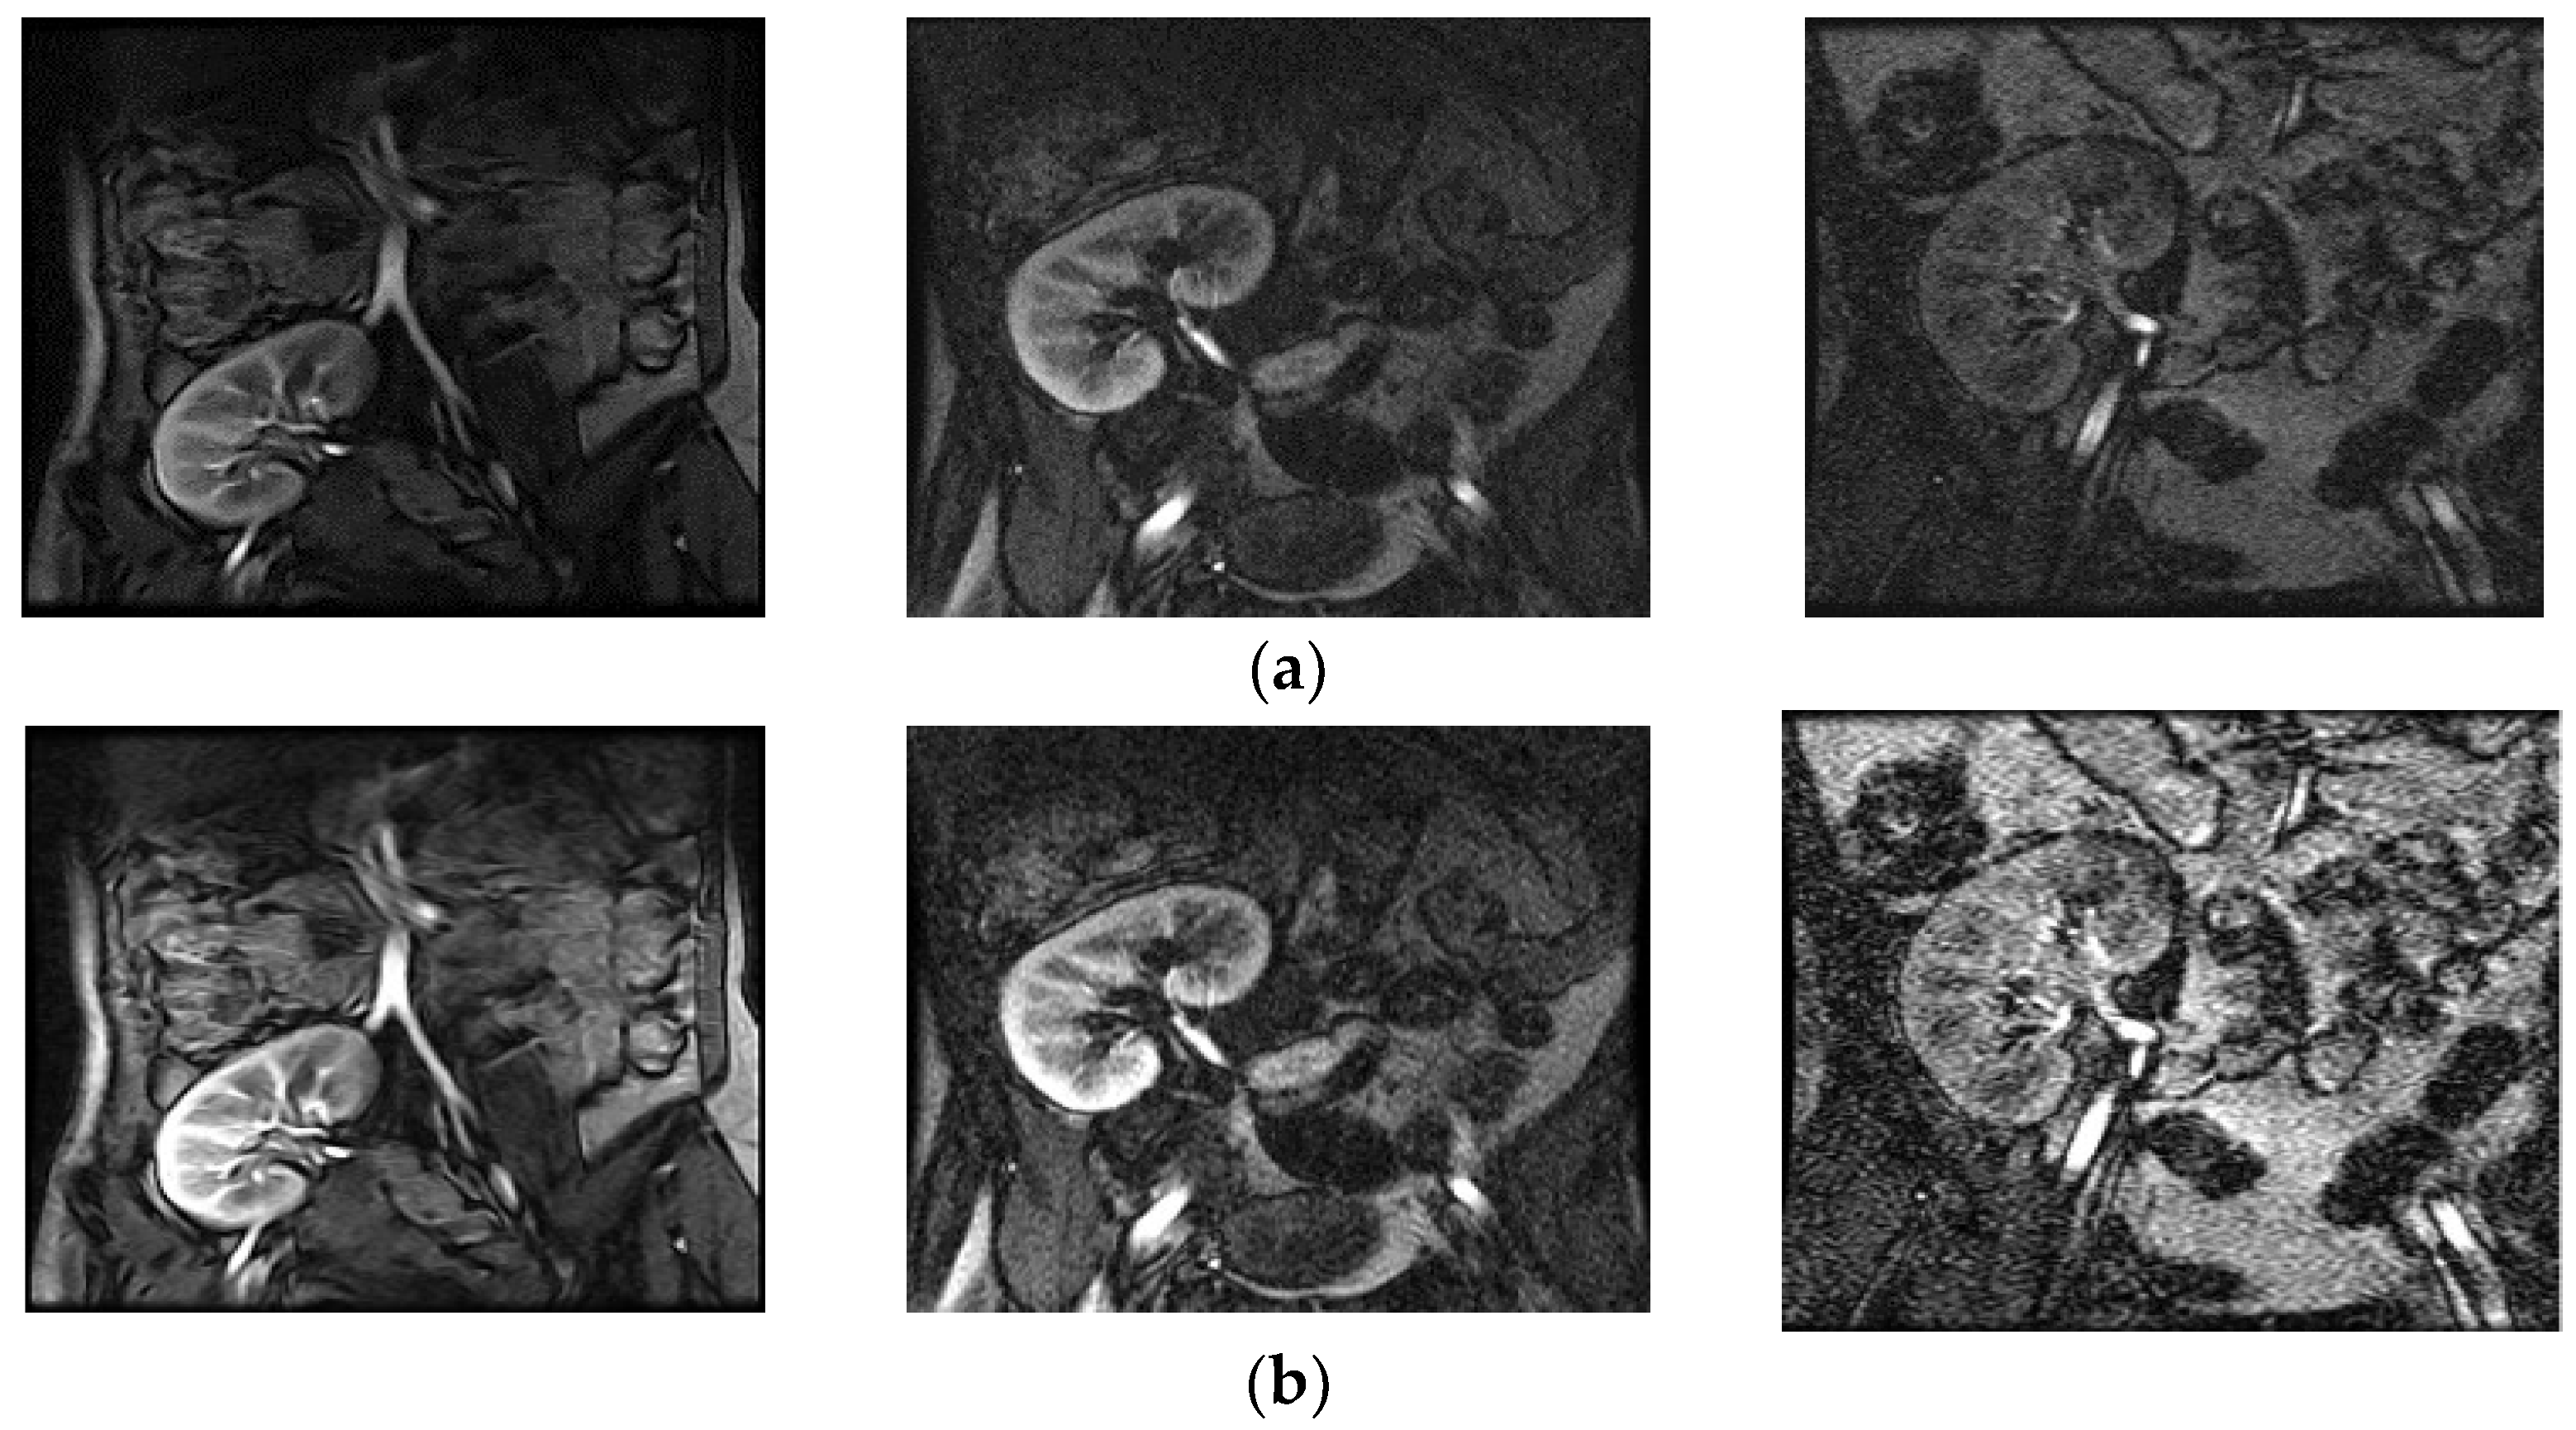

The above steps work well, because contrast enhancement of the input image is determined at each pixel depending on the probability of the pixel, which controls the changes in the gray values of the input image. Figure 2 shows a poor-quality input image with its enhanced counterpart, as well as graphs of their distribution of probability of pixels. It is noted from the enhanced image shown in Figure 2a that the contrast between background and boundary pixels of the kidney image is increased compared to the input image. This shows that the proposed model improves the overall quality of the image. It is evident from Figure 2b that the distribution of pixels’ probabilities for the input image before enhancement appears to be dense. Similarly, the distribution of pixels’ probabilities appears to be scattered in the enhanced image, which means the contrast has been stretched. Therefore, we can conclude that the low-contrast pixels, which represent boundaries of the kidney, are enhanced and hence result in scattered probability distribution with the same frequencies of the input image. Figure 3 shows the enhancing effect of the proposed model for a few more poor-quality kidney images. Input images are shown in Figure 3a, while the enhanced images are shown in Figure 3b.

Figure 3. The result of proposed enhancement model. (a) Input poor quality kidney images and (b) enhanced images.